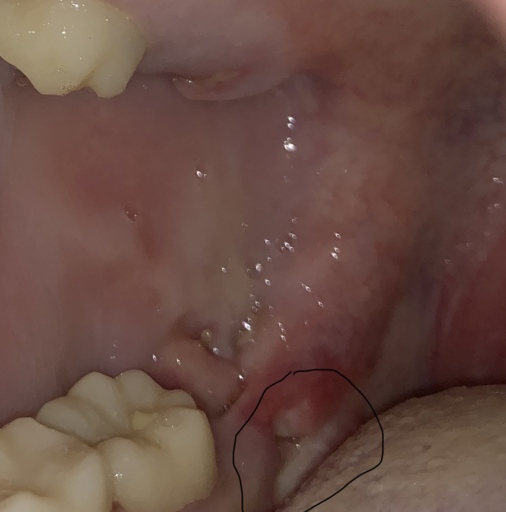

I have a very large cavity on one of my upper molars that caused severe pain for several weeks and went up through my sinuses. I live below the poverty level and have no insurance, but I headed to the ER because it was radiating out farther. I was put on penicillin and referred to our local, county health department where the only adult dental care offered is extraction. They have no anesthesia but did have Novocaine. He did an x-ray and said the roots were very deep but I know I don't have the option for a filling or root canal so I said that was fine. The Novocaine deadened every area of my mouth except the one nerve right in my tooth. I told him several times I was feeling pain, not pressure. After an hour of him attempting to extract the tooth, I had to have him stop because my whole body was shaking and I was sobbing no matter how much I tried to stop. I asked what now and there were no suggestions but he did inform me the tooth was still very firmly in my mouth and would not fall out on its own. For several days afterward, I had quite a bit of pain at the site of the injections (he injected in multiple locations 3 separate times)and the pain I had gone in with, though the radiating pain had stopped after completion of the penicillin. This was a month ago. I brush regularly and only use one side of my mouth to eat with because contact between the upper and lower teeth is very painful on the right side. This week, I have had some more aching but I figured I was just grinding my teeth again (yes, I have apnea and a bi-pap) but yesterday, the pain in the gum surrounding the tooth and roof of my mouth in the area where the dentist had done the injections returned as if he had been yanking on my tooth again. He did damage the tooth quite a bit during the attempted extraction with the ...pliers (not sure of the correct term) because I don't think he thought the tooth would be remaining. I am at a loss what to do now because I am already eating soft foods and the pain is bad enough, it woke me from sleep. I am taking an OTC NSAID, rinsing with salt water, and avoiding sugary or acidic foods. What else can I do?